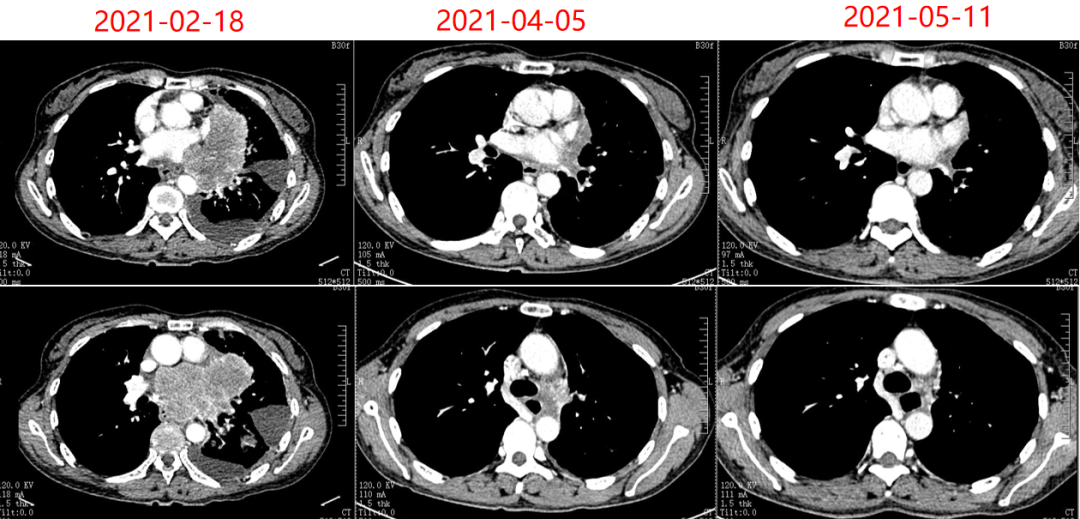

图5. CT复查结果

2022年3月23日行头颅MRI:提示头部出现转移病灶。肺部病灶稳定。与试验方沟通后,允许脑部病灶给予放疗,并继续原方案维持治疗。脑部放疗方案为PGTV:45GY,4.5GY/次,5次/周。至此,患者PFS1已达15个月。

2023年6月5日患者出现头部症状重,头脑不清楚,行MRI提示放射性脑坏死。此后患者出组,临床揭盲确认其属于替雷利珠单抗组。

2023年7月给予患者“贝伐珠单抗

联合化疗”治疗4周期后头部症状缓解。后继续替雷利珠单抗维持治疗,期间定期影像学随访,疗效维持PR。

最后一次影像学随访时间为2024年3月22日。此时,PFS2已超过39个月。

图6. 2024年3月22日CT结果

另一例患者为58岁女性,2020年12月体检发现肺占位。经检查确诊为广泛期小细胞肺癌(伴颅骨转移,ⅣB期)。该患者同样入组RATIONALE-312研究,接受“铂类+依托泊苷联合替雷利珠单抗或安慰剂”治疗,首次评估亦达PR。治疗过程中出现颅脑进展,经局部放疗后继续原方案治疗。后因放射性脑坏死退出研究,临床揭盲证实其隶属于替雷利珠单抗组。后续经贝伐珠单抗联合化疗,头部症状缓解后继续替雷利珠单抗治疗,疗效始终维持PR。至2024年3月22日末次随访,其PFS2已超过39个月。